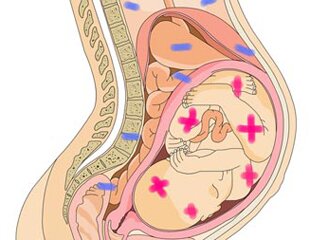

Как правило, наличие резус-конфликта между кровью матери и ребенка в течение первой б Далее...

Невынашиванием беременности называют самопроизвольное ее прерывание на сроке до 37 не Далее...